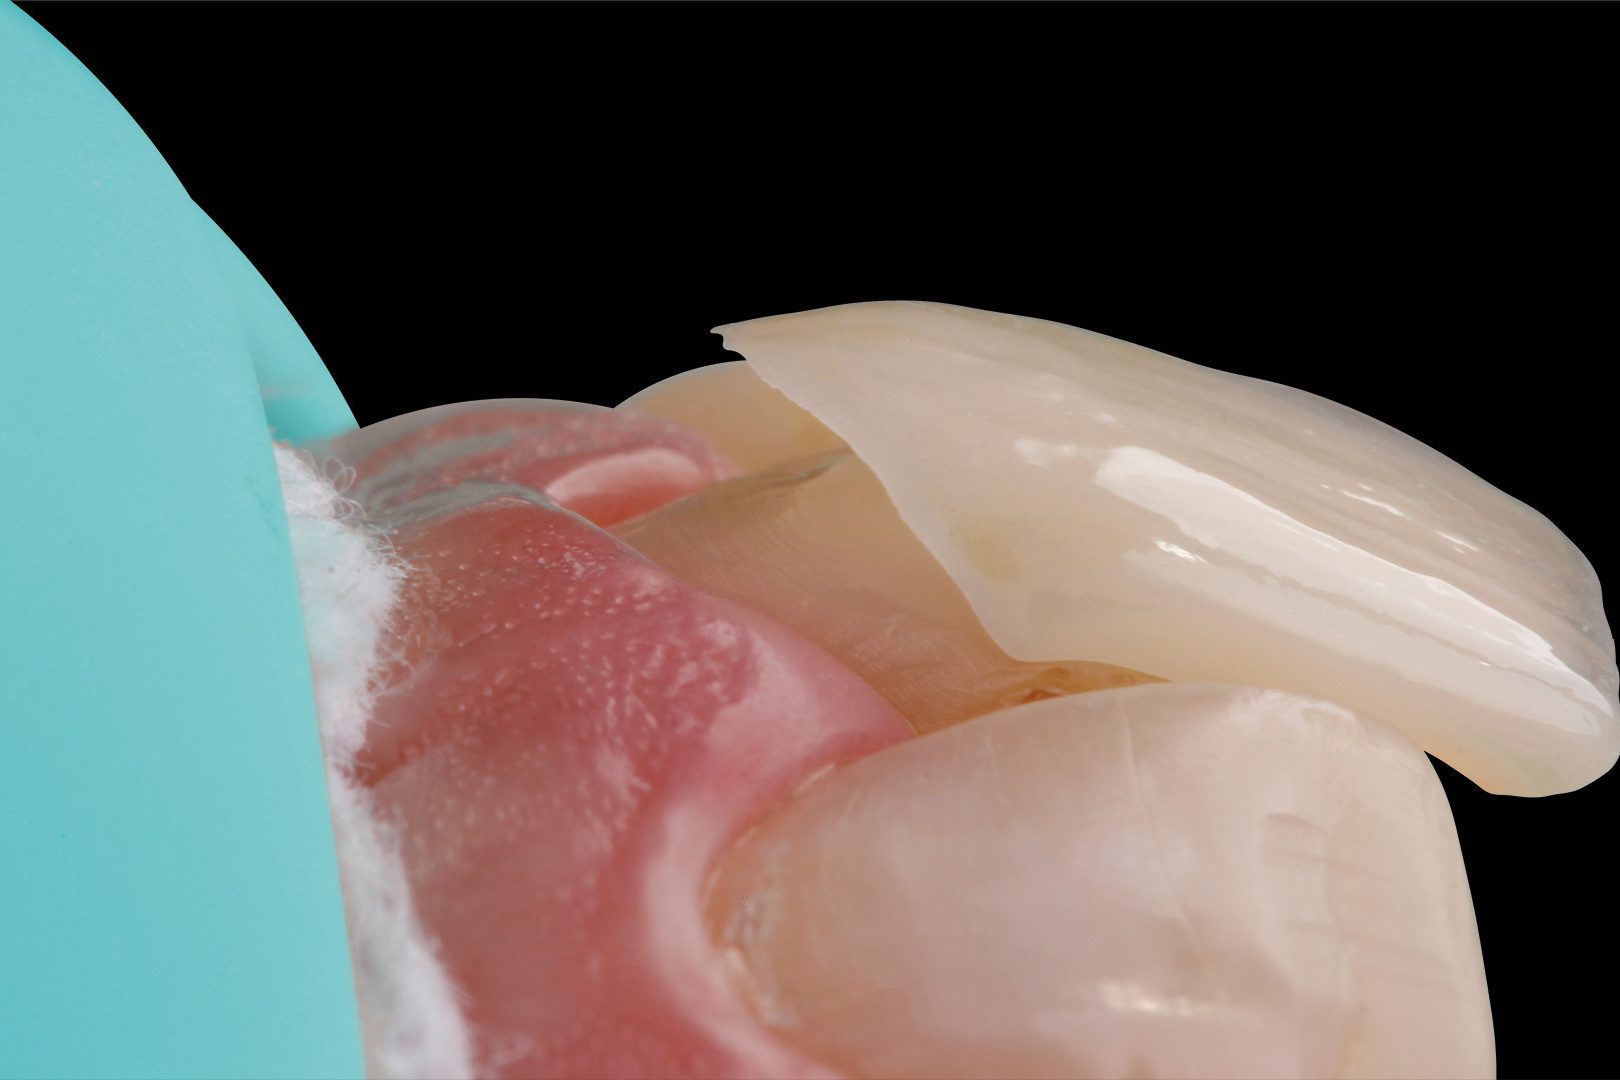

- Based on the patient-specific model articulation and the selection of a digital Monsons Sphere with Ø 240 mm, the areas to be prepared in the occlusal region were highlighted and a preparation guide for the upper jaw was created. After determining the centric relationship, it turned out that, due to the new occlusal height, the canine 23 needed a palatal support surface to optimise function. Therefore, a vestibular and a palatal veneer were designed to avoid too invasive preparation of the natural tooth. During cementation, the vestibular veneer was applied first, and then the palatal one (‘sandwich technique’)

- Production of Prettau Skin veneers in Prettau 3 Dispersive zirconia with a minimum thickness of 0.2 mm

- Adhesive cementation of the final restorations; manufacture of a transparent splint to protect the zirconia restorations